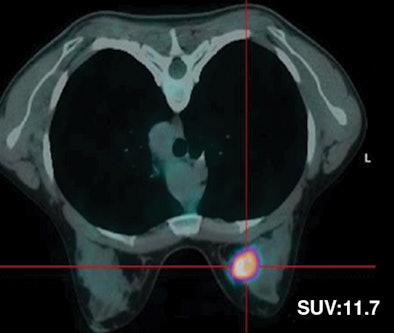

| Thirty-two-year-old woman with ductal infiltrating adenocarcinoma measuring 18 mm in maximum transverse diameter. Axial fused PET/CT images obtained with patient in prone position at time point 1 (above) and time point 2 (below) show corresponding standard uptake values. |